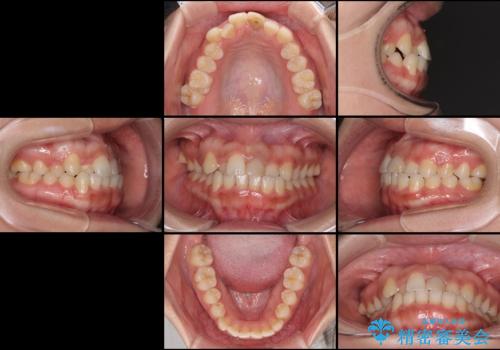

前歯の反対咬合 非抜歯のワイヤー矯正

- 前歯のでこぼこを気にして来院された患者様です。

マウスピース矯正の自己管理が面倒くさいことと、治療を早く終わらせたいとのことで、目立ちにくいワイヤー矯正にて歯列を整えることとしました。